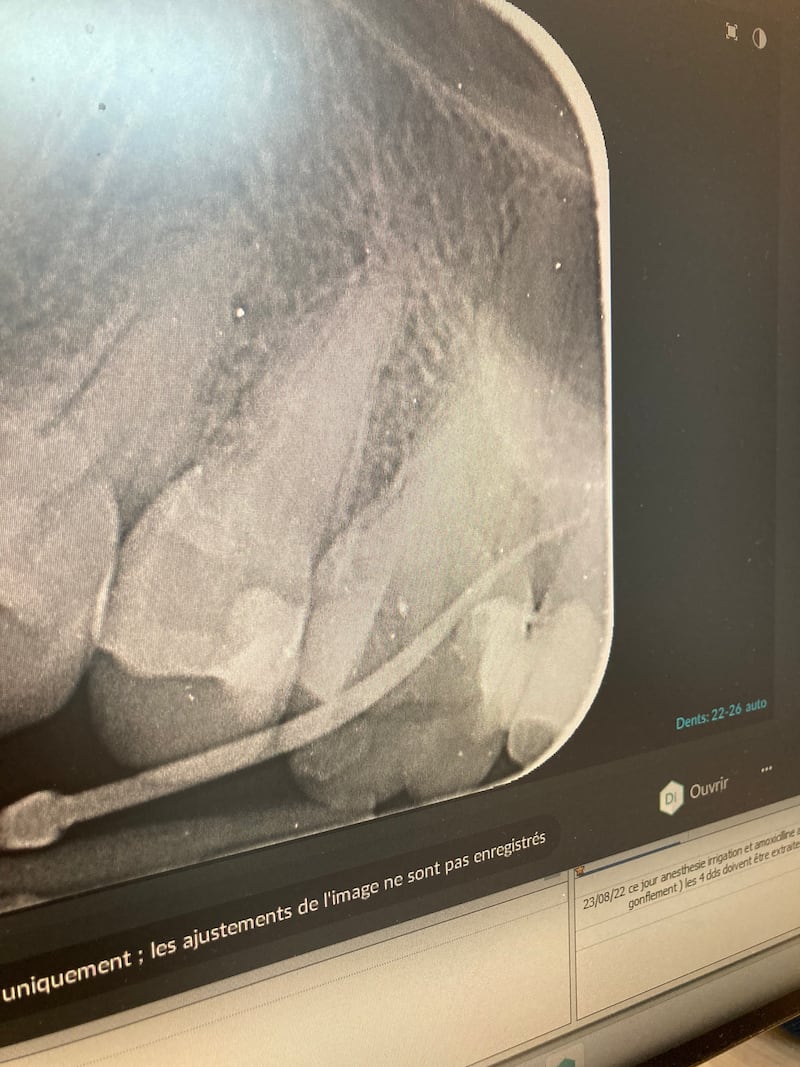

sur la radio je n'arrive pas à être certaine si la longueur semble bonne et si je suis le canal ou en dehors

qu'en pensez vous ?

Si tu es en dehors du canal c'est que tu as perforé et - généralement - ça saigne.

Mais bon, la radio n'est pas très orthogonale... ;-)

Ça a l’air perforé oui mais en même temps on voit rien, essaye au moins de prendre une photo en face de ta radio :)

Difficile de se prononcer sur une radio aussi pourrie, à fortiori sur une photo d'écran d'ordi.

Ça a bien l'air perforé qd même

Y’a rien qui va dans ce sujet entre la photo de l’écran de 3/4, la grosse perfo et l’auteur qui se demande si il est a la bonne LT…

mon avis c est que cette dent est condamnée, t as bien perforé (et ca arrive...) et que l obturation de la perf va être difficile, se rajoutant a la difficulte de traiter les racines vestibulaires...

Tu as pris ta longueur de travail avec quelle lime ? Parce que pour perdre le localisateur d'apex à ce point, je me demande ce qui a pu bugger. Apres les perfos ca arrive ... Pas plus tard qu'hier sur le RTE de 35 ...

Si tu as vraiment utilisé un localisateur d’apex, si c’est une perfo ça sonne.

Le MV 2 me parait bien peu alésé.

Déjà, vu que tu as fait une cavité d'accès correcte, l'angulation de ton cône à l'extérieur de la cavité, même avec un canal très déporté ne sera jamais aussi importante si tu es dans le canal.